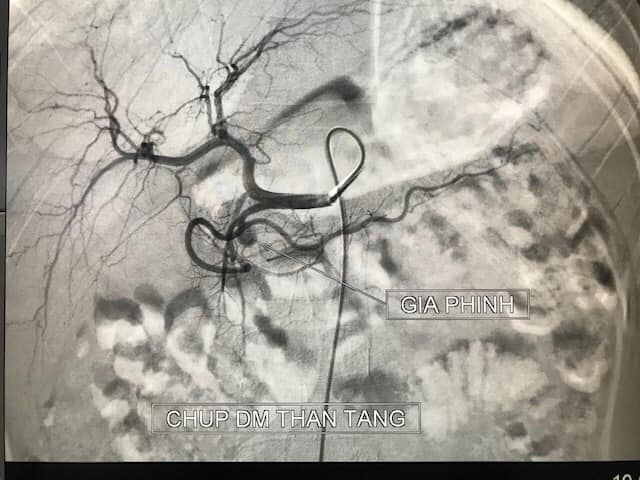

Hình ảnh ổ giả phình động mạch do viêm tuỵ cấp hiếm gặp ở trẻ 11 tuổi

Bé được đưa vào viện trong tình trạng nôn ra máu nhiều lần không tự cầm. Trên phim chụp cắt lớp vi tính cho thấy ổ giả phình lớn động mạch vị tá tràng (có chức năng cung cấp máu cho tá tràng – tụy và dạ dày). Các bác sĩ nhận định đây là trường hợp nặng, nguy cơ chảy máu ồ ạt đe dọa tính mạng nên bệnh nhi đã được can thiệp mạch cấp cứu ngay. Sau 20 phút can thiệp toàn bộ năm ổ giả phình đã được loại bỏ hoàn toàn, bệnh nhi hết nôn ra máu, huyết động ổn, và được chuyển về Khoa Nhi tiếp tục điều trị tình trạng viêm tụy cấp.

“Viêm tụy cấp có thể xảy ra ở nhiều mức độ nặng – nhẹ khác nhau và có thể để lại những biến chứng vô cùng nguy hiểm trong đó có tổn thương mạch máu dẫn đến ổ giả phình động mạch. Những ổ giả phình mạch phá vỡ cấu trúc mạch máu bình thường, gây chảy máu ồ ạt, thậm chí đe dọa tính mạng chỉ trong vài giây. Can thiệp mạch là phương pháp được lựa chọn để điều trị các tổn thương giả phình mạch do viêm tụy cấp với tỷ lệ hiệu quả, thành công và độ an toàn cao”, Lê Thanh Dũng giải thích.